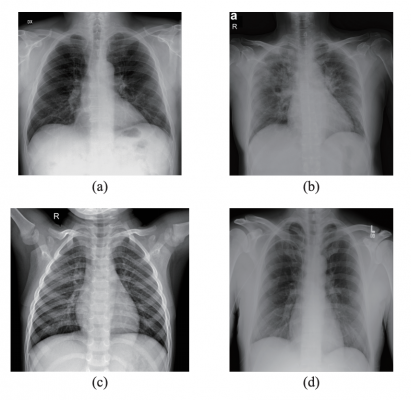

Samples from the dataset used in this study. (a) X-ray with PA view of a patient with COVID-19; (b) X-ray with AP view of a patient with COVID-19; (c) X-ray of a healthy patient from Dataset A; (d) X-ray of a healthy patient from Dataset B. Images courtesy of IEEE/CAA JOURNAL OF AUTOMATICA SINICA

However, the researchers found a lack of publicly available chest X-rays to train their artificial intelligence model to automatically identify the lungs of COVID-19 patients. They had just 194 COVID-19 X-rays and 194 healthy X-rays, while it usually takes thousands of images to thoroughly teach a model to detect and classify a particular target. To compensate, they took a model trained on a large dataset of other X-ray images and trained it to use the same methods to detect lungs likely infected with COVID-19. They used several different machine learning methods, two of which resulted in a 95.6% and a 98.5% accuracy rating, respectively.